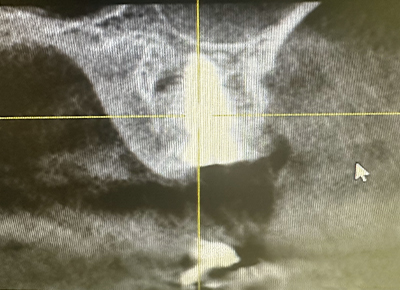

Fig. 04 : radio post-opératoire.